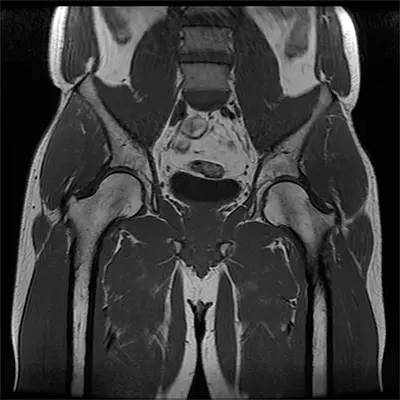

Diagnosis

Because lateral hip, thigh, or knee pain can arise from multiple causes, accurate diagnosis is critical. Dr. Domb and his team use a combination of physical examination, medical history, and imaging tests, which may include:

- MRI Scan: Detects soft tissue, muscle, tendon, and ligament damage